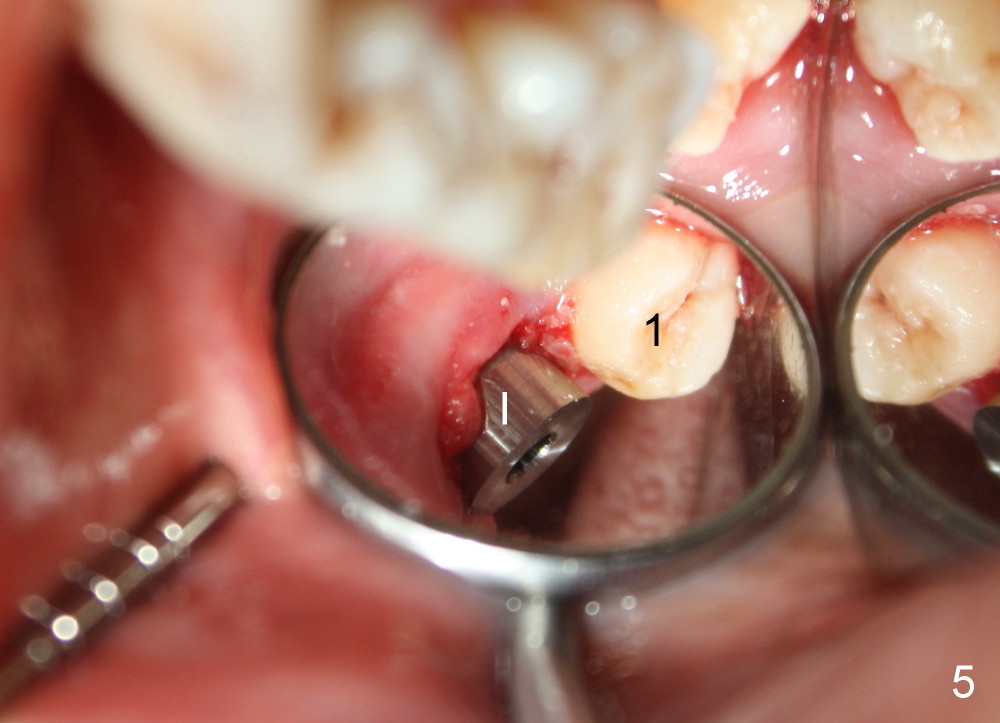

A 48-year-old lady is a dental phobic and has generalized chronic periodontitis. Bone loss around the tooth #2 has been severe for the last 5 years (Fig.1,2 *). Finally she agrees to have #2 (symptomatic) extracted and immediate implant placed (Fig.3 I). A 7x17 mm implant has to be used to achieve primary stability. The remaining buccal and lingual gaps are filled with allograft and membrane (Fig.4 *). Fig.5 shows that there is a space between the tooth #1 (asymptomatic) and the immediate implant (I). The wound/socket is protected by applying perio dressing around an abutment (Fig.6 A). Postop the patient is pain free; the perio dressing dislodges by itself. She returns 3.5 months later for restoration; but the tooth #1 has shifted mesially (Fig.6 arrow). The patient is not so willing to have #1 removed. Bands and bracket are placed in the neighboring teeth including a provisional crown to move the shifted tooth (with mobility) distally (Fig.7,9). The 2nd reason for #1 shifting is abnormal occlsual scheme on the right posterior region (Fig.8); mobility of #1 is the 1st one. The 3rd one is probably bruxism. In 5-6 weeks, the tooth #1 has moved to a desirable position (Fig.10, as compared to Fig.3,5). There is enough space for restoration (Fig.11,12).